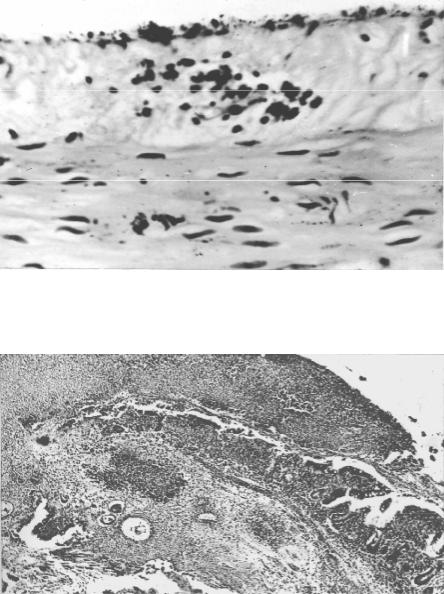

в

а

б

г

д

Рис. 25. Синегнойная и энтеробактериальная гнойные раневые инфекции (окраска гематоксилином и эозином а, д, азуром II и эозином б, в, г): а очаг синегнойной инфекции с явлениями гнойного тромбоваскулита и распро- страненным некрозом в гранулирующей ране (× 100); б скопления грамот- рицательных палочек Pseudomonas aeruginosa (синегнойной палочки) в мазке отпечатке из той же раны (×1000); в очаг энтеробактериальной инфекции в ране со скоплением лейкоцитов вокруг некроза с прорастающими его коли- формными микробами (палочками) (× 400); г грамотрицательные палочки (энтеробактерии) в мазке-отпечатке из той же раны (× 1000); д парафасци-

альное распространение воспалительного процесса при энтеробактериальной инфекции в глубину тканей (× 200)